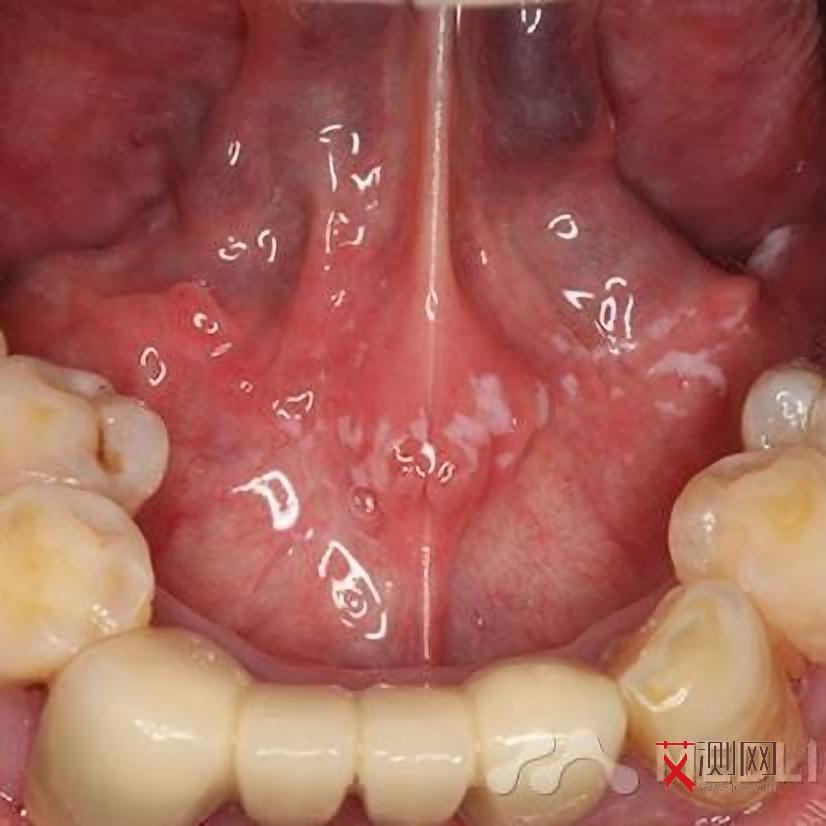

- 皮肤问题:如反复出现的口腔溃疡、真菌感染或带状疱疹。

- 生殖系统症状:月经紊乱、女性生殖器,念珠菌感染或盆腔炎。

女性感染者还可能出现生殖系统机会性感染,如宫颈念珠菌病、盆腔结核或人乳(和谐)头瘤病毒相关癌症风险增加。